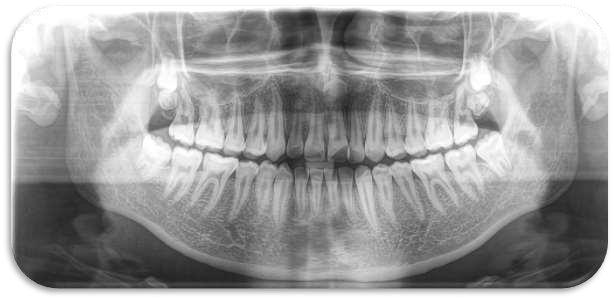

FIGURA 1 (TOMOGRAFIA VISTA FRONTAL)

Los caninos retenidos constituyen una anomalía eruptiva frecuente que requiere atención interdisciplinaria. El diagnóstico temprano mediante exploración clínica y radiográfica es esencial para prevenir complicaciones y planificar un tratamiento adecuado. La combinación de ortodoncia y cirugía representa la opción terapéutica más utilizada, con un pronóstico favorable si se actúa de manera oportuna

FIGURA 2 (PERIAPICAL PZA. 1.3)